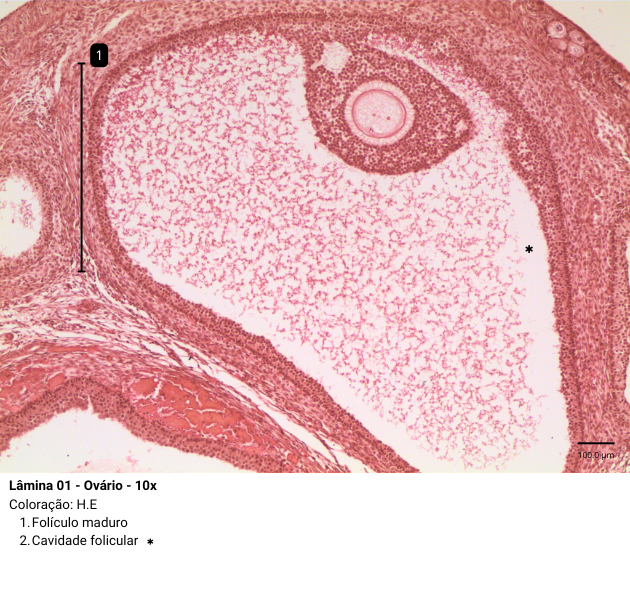

- Folículo maduro (pré-ovulatório ou de Graaf): O folículo maduro ou dominante, é o folículo que se encontra no estágio máximo de desenvolvimento e que prossegue até a ovulação. Seu tamanho é proeminente, cerca de 2,5 cm, chegando a formar uma protuberância que pode ser detectada por ultrassom. Com o progressivo acúmulo de líquido, ocorre aumento da cavidade folicular seguido de afinamento da camada da granulosa, uma vez que essas células não proliferam proporcionalmente ao crescimento cavitário. Esse acúmulo, também, leva ao afastamento do cumulus oophorus de sua base, onde permanece flutuando livremente no líquido folicular.

Nessa imagem, é possível visualizar o folículo maduro com a presença da cavidade folicular.